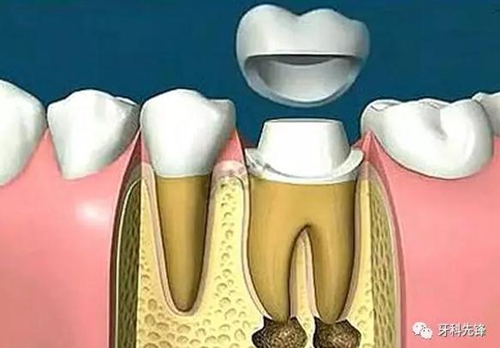

根管治療后需要做牙冠,原因有三

1、因?yàn)樾枰M(jìn)行根管治療的牙齒,一般已經(jīng)是蛀牙缺損很大,這個(gè)時(shí)候雖然根管治療完成,但是剩下的牙體組織非常脆弱,容易折斷、裂開,失去正常的功能,單純用材料已經(jīng)沒法恢復(fù)功能。

2、根管治療是以藥物,以及器械的操作來將根管內(nèi)的殘?jiān)?,以及?xì)菌盡可能地清除消毒干凈。然而,這樣的消毒過程如果要認(rèn)真的進(jìn)行,卻必須去除掉不少被細(xì)菌感染的牙齒,以及不得不修正的牙體組織。所以大部分的牙齒一旦進(jìn)行根管治療,則可能不太足夠支持咀嚼的力量而可能斷裂,單純用材料已經(jīng)沒有辦法恢復(fù)功能,即使能恢復(fù)長(zhǎng)遠(yuǎn)效果也不好。

3、經(jīng)過根管治療后的牙齒失去了來自牙髓的營養(yǎng)供應(yīng),就像失去樹根的樹木一樣,慢慢枯萎變的很脆弱,造成牙齒的脆性增加,易劈裂。

由于這3個(gè)方面的原因,整個(gè)牙齒的支持力量明顯減弱,可能在某些特定條件下不足以支持咀嚼壓力而容易發(fā)生牙冠劈裂,所以要及時(shí)做個(gè)牙冠把牙齒保護(hù)起來。